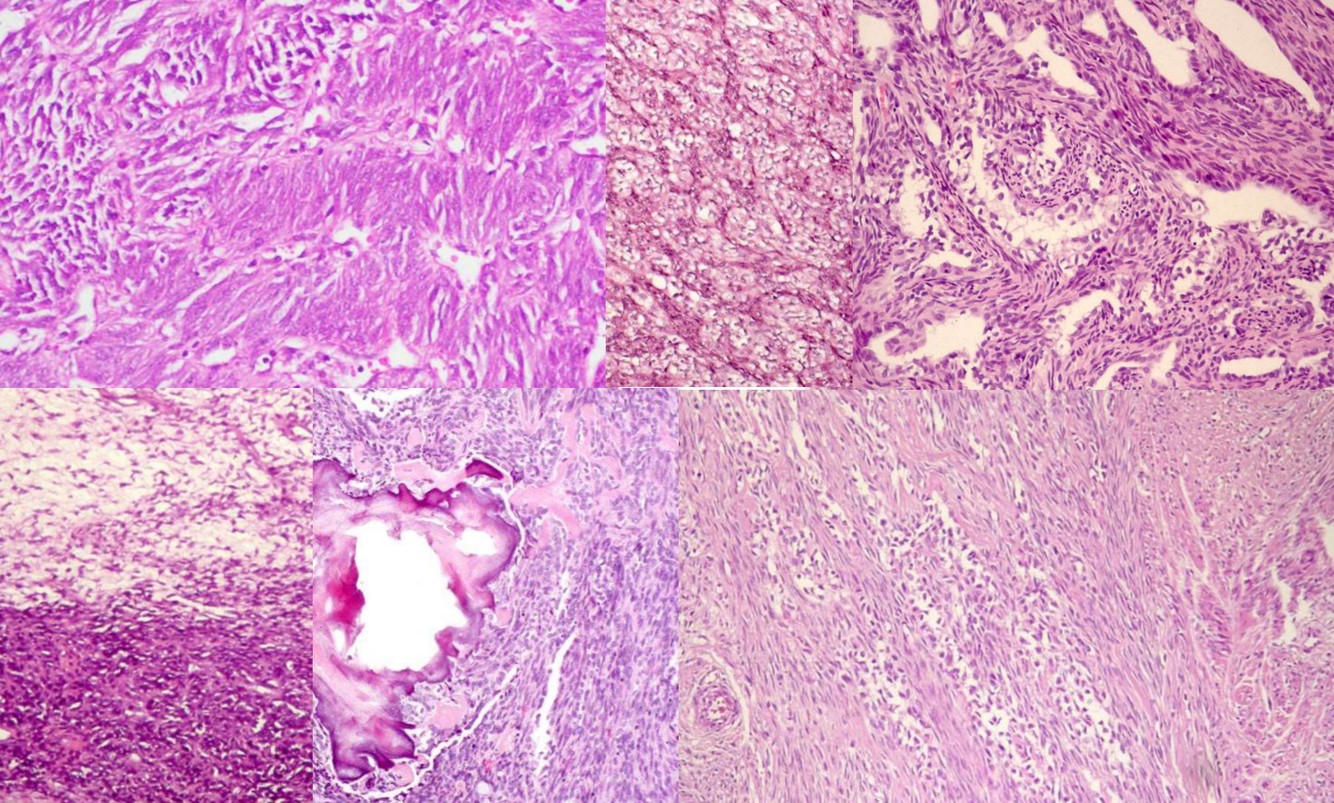

ATYPICAL FIBROXANTHOMA

• Seen primarily in the elderly population

• Predilection for sun-exposed skin, especially scalp and ear

• MFH-like tumor of the dermis

• Histology

• Well circumscribed, appears symmetric at scanning magnification

• Bizarre multinucleated tumor cells in hypercellular, spindly stroma with frequent mitotic figures, many atypical

• Also smaller fibroblastic, myofibroblastic and histiocyte-like cells with pleomorphism and angulated nuclei

• Histologically identical to MFH-pleomorphic but centered in dermis

• Background stroma appears inflammatory or reactive

• Pushes aside pilosebaceous units and eccrine glands

• Typically does not involve epidermis or subcutaneous tissue

• Lacks classic features of fibrous histiocytoma (entrapped hyalinized collagen bundles and epidermal hyperplasia)

• No grenz zone, no necrosis, no vascular invasion, no infiltrative margins

• Stains

• Positive: Vimentin, and p53

• Negative: Cytokeratin, S-100, Desmin or smooth muscle actin, LN-2 antibody (CD74)

• Diagnosis of exclusion – need to exclude the diagnosis of melanoma

• Excellent prognosis

Undifferentiated pleomorphic sarcoma

• Pleomorphic sarcoma composed of fibroblasts, myofibroblasts and histiocyte-like cells

• Diagnosis of exclusion; must sample generously and search for other components to rule out a dedifferentiated tumor or evidence of specific differentiation other than fibroblasts or myofibroblasts

• Usually older adults (age 50+ years) with slight male predominance; more common in lower extremities, rarely retroperitoneum, head and neck, breast

• Large and deep-seated with progressive enlargement

• Sarcomas adjacent to orthopedic implants or post-radiation are usually osteosarcoma or MFH

• Pleomorphic and bizarre tumor cells with foamy cytoplasm and marked atypia, in background of inflamed collagenous stroma

• Histologic types: storiform/pleomorphic, giant cell, inflammatory, myxoid

• Numerous mitotic figures, including atypical forms

• Rarely metaplastic (not neoplastic) bone or cartilage